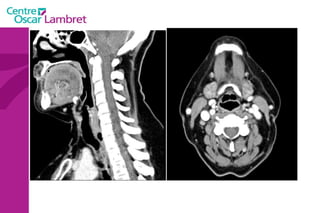

Les  artères Carotides Communes  : La droite vient du TABC. La gauche vient de la crosse de l’aorte. Elles n’ont aucune branche collatérale. L’appareil circulatoire

L’artère carotide primitive droite : Elle naît à 3 cm en arrière de l'articulation sterno-claviculaire à la hauteur de T1. monte dans la gouttière carotidienne le long de la trachée et du corps thyroïdien, de l'oesophage puis du larynx et du pharynx.  Elle s’évase avant sa terminaison en regard du bord supérieur du cartilage thyroïde et de C4.  L’appareil circulatoire

L’artère carotide primitive gauche  : naît directement de la crosse aortique et comporte un premier segment intra thoracique en arrière du manubrium sternal. Son segment cervical est identique à celui de la carotide primitive droite.  L’appareil circulatoire